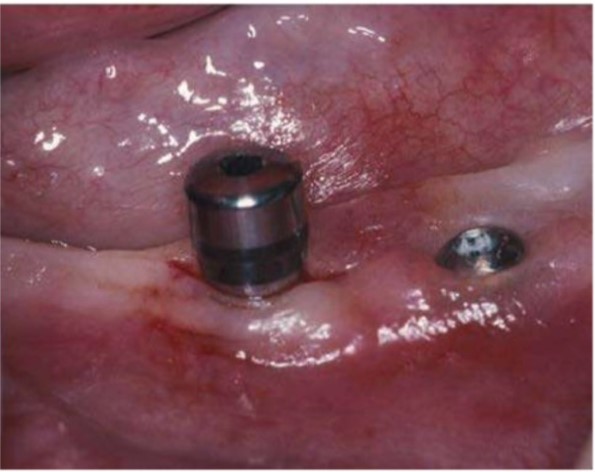

Thiết kế vạt khi phẫu thuật đặt abutment rất quan trọng vì nó tạo cơ hội cho phẫu thuật viên điều chỉnh hình dạng mô mềm. Nhiều quan điểm phát sinh cũng được áp dụng khi xử lý vạt trong phẫu thuật đặt implant không vùi. Nhìn chung, đường rạch được đặt trực tiếp ngay trên đầu implant trừ phi phẫu thuật viên muốn dịch chuyển phần mô sừng hóa thiên về một phía nào đó hơn. Ở phần hàm tiêu xương tái diễn trầm trọng có rất ít mô sừng hóa, điều quan trọng là phải bảo tồn được tất cả phần mô này, và một số trường hợp đòi hỏi phải ghép mô mềm. Đường rạch đỉnh sống hàm nhỏ ngang qua đầu implant và bóc tách mô mềm tối thiểu để đặt abutment sẽ dễ dàng hơn với những hệ thống có kết nối abutment-implant là kết nối trong, chẳng hạn như Astra.

Đường rạch nhỏ qua implant Astra cho phép gắn trụ lành thương. Implant bên phải được bộc lộ vít lành thương.